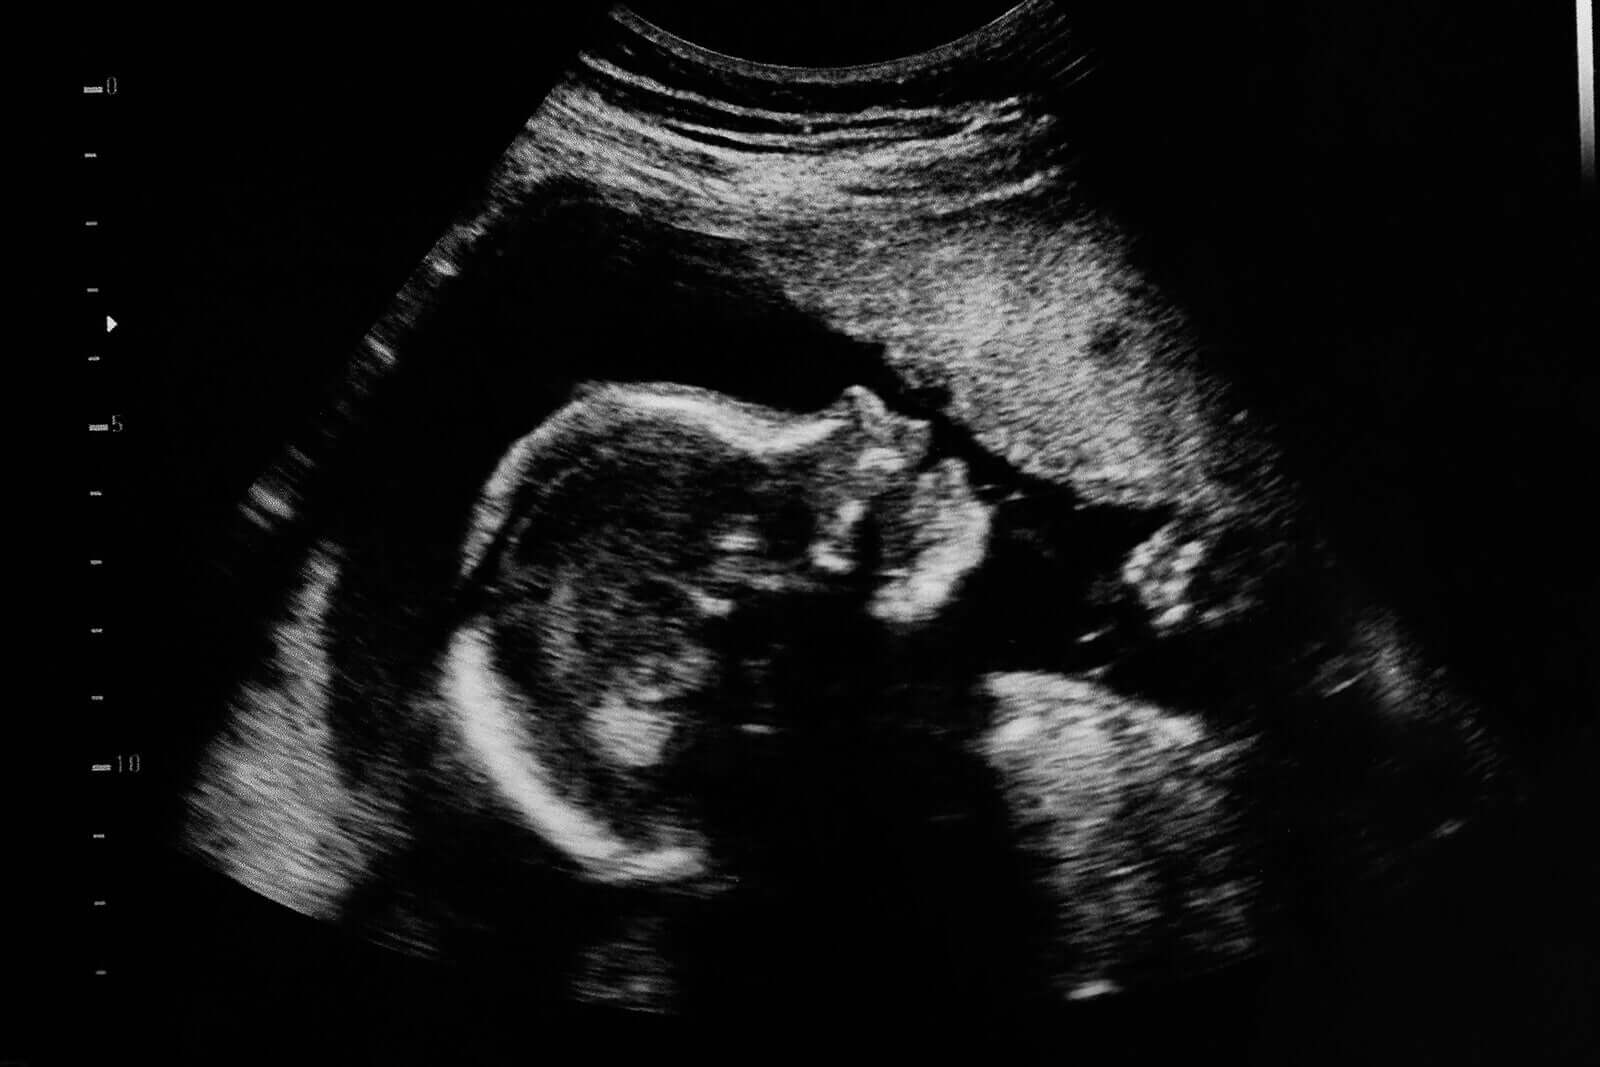

Alle foreldre gleder seg over å se babyen deres “svømme” inne i livmoren. Enda mer når spesialisten som utfører studien informerer dem om at alt ser ut som forventet, men har du noen gang lurt på hva som ville skje hvis meldingen var det motsatte?

Utover de vakre detaljene på bildet i forgrunnen, bør du alltid huske på at graviditetsultralyd er medisinske studier for å diagnostisere nøyaktige problemer. De er ikke og bør ikke brukes på noen måte som fotografiske sesjoner av det ufødte barnet.